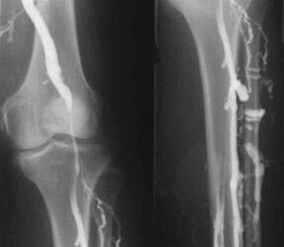

Visizplatītākā instrumentālās diagnostikas metode ir kāju venozo asinsvadu ultraskaņas izmeklēšanas izmantošana. Šis paņēmiens ļauj vizualizēt asinsvadu sistēmu un noteikt patoloģiskā procesa progresa pakāpi.

- Flebogrāfija.

- Fotopletismogrāfija.

Vēnu oklūzijas pletismogrāfijas izmantošana ļauj noteikt asins tilpumu apakšējo ekstremitāšu vēnās.